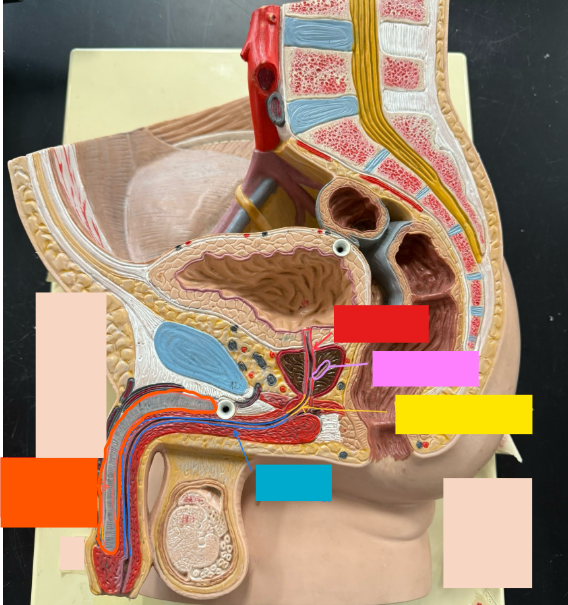

What is the name of the red box?

Ureter

What is the name of the red box?

Vas deferens

What is the name of the yellow box?

Seminal vesicle

What is the name of the blue box?

Prostate

What is the name of the light blue box?

Prepuce

What is the name of the blue box?

Corpus spongiosum

What is the name of the black box? X2

Prostate

What is the name of the purple box?

Rectum

What is the name of the yellow box?

Anus

What is the name of the red box?

Prostatic urethra

What is the name of the pink box?

Ejaculatory duct

What is the name of the yellow box?

Membranous urethra